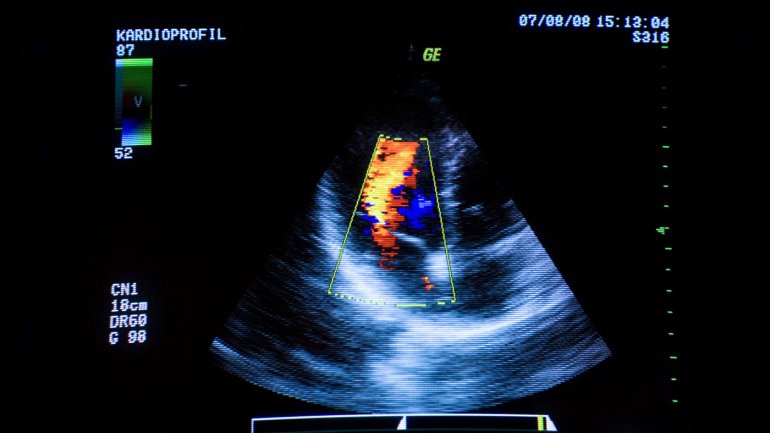

Man sieht eine Herzultraschall-Aufnahme.

© Jupiterimages/Hemera

Echokardiographie (Herzultraschall)

Je nach Fragestellung kommen bei der Echokardiographie verschiedene darstellende Methoden zum Einsatz: vom eindimensionalen M-Mode-Verfahren über das zweidimensionale B-Mode-Verfahren bis zur farbkodierten zweidimensionalen Duplex-Sonographie, mit der auch Richtung und Geschwindigkeit des Blutflusses erkennbar werden.